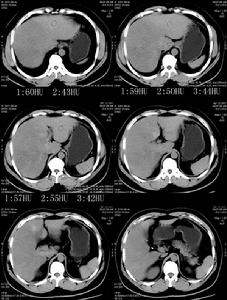

臨床上可按圖3所示Bartter綜合徵診斷步驟來逐步確診該病。

![]() |

| 圖3 |